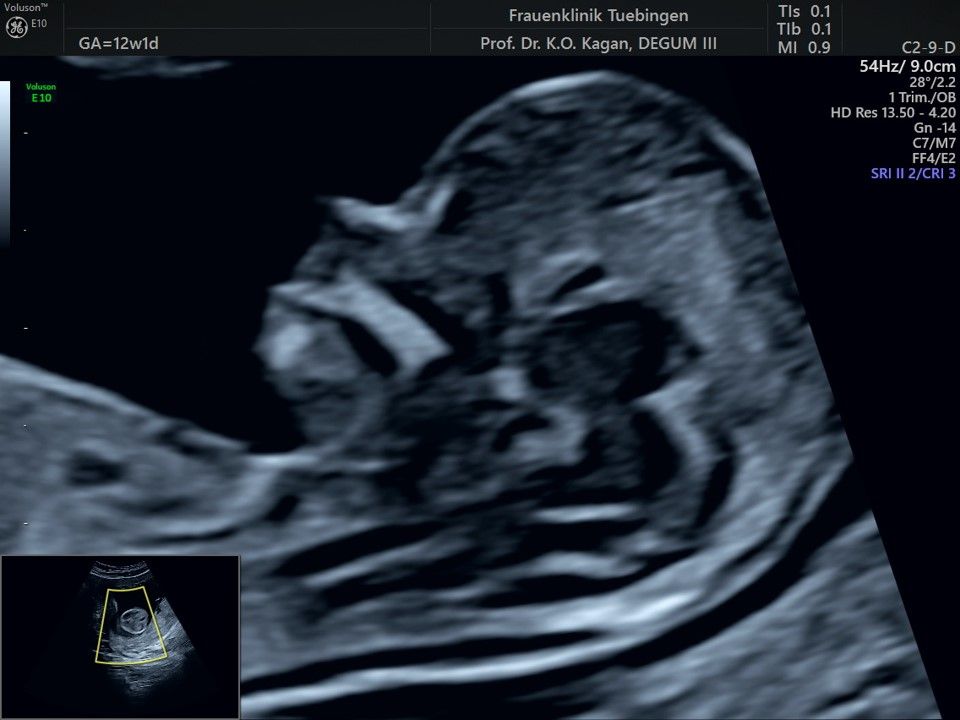

Im Rahmen des Ersttrimester-Screenings untersuchen wir die Organe des Feten mittels Ultraschall. Dabei machen wir auch gerne ein Bild für Sie.

Obwohl der Fet zu diesem Zeitpunkt erst zwischen 5 und 8cm groß ist, lassen sich bereits etwa die Hälfte aller schwerwiegenden Fehlbildungen erkennen bzw. ausschließen. Sollten wir eine Auffälligkeit sehen, werden wir mit Ihnen den Befund und das weitere Vorgehen ausführlich besprechen.

Das Ergebnis der Ultraschalluntersuchung ist wegweisend. Dabei wird der Fet vermessen, die Organe werden untersucht und die sonographischen Marker zur Risikoberechnung für Chromosomenstörungen werden beurteilt. Das sind: die Nackentransparenzdicke, Nasenbein sowie der Blutfluss in der rechten Herzhälfte und im Ductus venosus, einem Gefäß in der Leber des Feten.